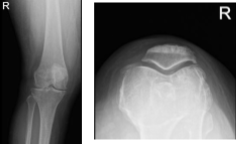

She presented her Xray results, for her left knee there are mild osteoarthritic degenerative changes. For the right knee, there are moderate osteoarthritic degenerative changes. There are no fractures and there are no acute fractures.

XR of Right Knee Lateral Oblique View